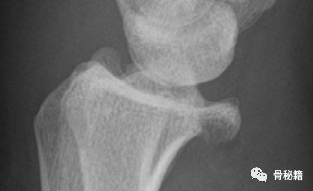

掌侧的一个边缘剪切骨折伴有脱位,采用边缘克氏针固定。

可见骨折固定良好,关节稳定